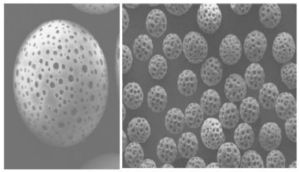

従来のPLLA製剤は粒子構造が粗く、炎症やしこりの原因となりましたが、プレナフィルは粒子構造を極限まで均一な球体に構成したことで、炎症やしこりのリスクを軽減しています。

副作用が少ない

プレナフィルは、鋭い形をした他のポリ乳酸製剤と異なり、丸型の粒子をしています。そのため異物反応が起こりにくく、肉芽形成やしこりといった副作用のリスクが少なくなりました。